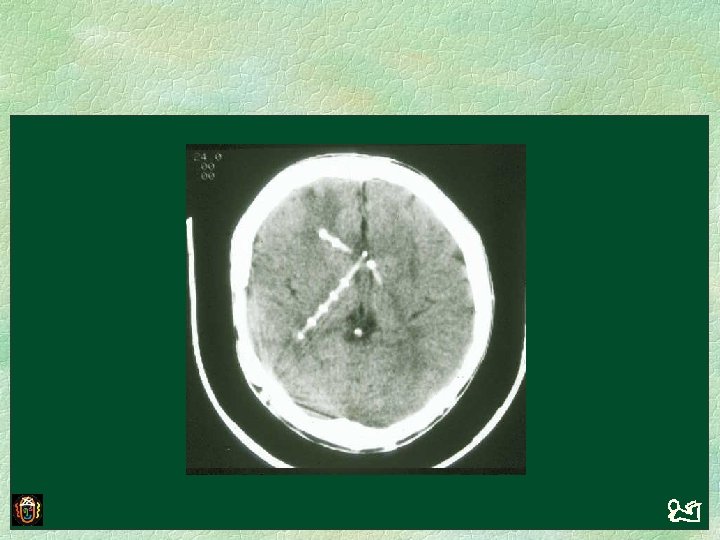

Same patient, GCS 12